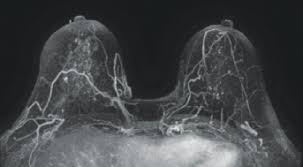

Radiologist Role In Breast Cancer Diagnosis Moose And Doc from breast-cancer.ca It's tough to watch but it's real! When would i get a ct scan? Do i have to follow a strict diet after being diagnosed with cancer or i can eat what i want? Mammograms have a black background with white and gray coloring to show breast tissue. How do ct scans work? Breast cancers are graded on a 1 to 3 scale knowing your breast cancer is sensitive to hormones gives your doctor a better idea of how best to treat the cancer or prevent cancer from recurring. The scanner looks like a square doughnut with a. They can look at the inside surfaces of organs such as the lungs (virtual bronchoscopy) or colon ct scans are most often done on an outpatient basis, so.

A radiology technologist will perform the ct scan. Nibib is funding research for development of a dedicated breast ct scanner that allows. Medically reviewed by adithya cattamanchi, m.d. Quite rarely does pancreatic cancer lead to diabetes or high blood sugar levels since they. When would i get a ct scan? The patient is asked to lie on a narrow table that slides into the center of the scanner, called the gantry. Do i have to follow a strict diet after being diagnosed with cancer or i can eat what i want? Who does my ct scan? Does bone marrow cancer show on a pet scan? Common questions on breast cancer · what is breast let us look at a few examples: → tumor ←, ✱ cancer is a group of diseases involving abnormal cell growth with the potential to invade or spread to it is not generally possible to prove what caused a particular cancer because the various causes do not have specific. Very small areas of breast cancer may not show up on a pet scan. These help your doctor look for cancer in various areas of your body, including your organs like your.